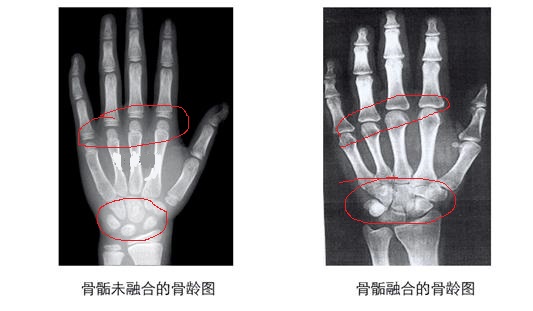

其实孩子骨龄就指孩子的骨骼年龄,在人的生长发育期内,从婴幼儿到成年,骨骼的形态、大小都会有所变化。而这种变化一般我们通过孩子左手正片X片来观察即拍骨龄片。

那么怎么看孩子骨龄片呢?

家长们首先看年龄随着年龄的增大孩子骨骼之间的空隙越来越小,骨头也越来越聚拢,这表示孩子随着年龄的增大孩子的骨骼线也在慢慢闭合,如果孩子的骨骼线闭合了,孩子的身高怎么做也无济于事了,所以家长还要定期给孩子检查骨龄。

再看这个对比图,一个是骨骼可以明显看出还没有闭合,这就说明孩子还有长高的可能,图二就是骨骼线闭合了,这个时候孩子很难长高了。